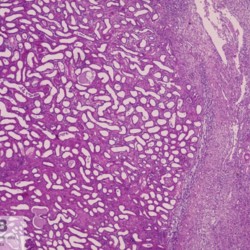

Etiquetes: B-590/92 3 total Canine Specie: Canine Organ: Kidney Lesion: Dysplasia Lesion modifier: - Disease: Juvenile nephropathy Files/Expedient: B-590/92 Not viewed Canine Specie: Canine Organ: Kidney Lesion: Dysplasia Lesion modifier: - Disease: Juvenile nephropathy Files/Expedient: B-590/92 Not viewed Canine Specie: Canine Organ: Kidney Lesion: Dysplasia Lesion modifier: - Disease: Juvenile nephropathy Files/Expedient: B-590/92 Not viewed Títol Select...Avian (Exotic) (110)Avian (Poultry) (76)Bovine (317)Canine (935)Caprine (47)Equine (257)Feline (326)Ferret (19)General (127)Marine mammal (22)Non-human primate (20)Ovine (328)Porcine (379)Rabbit (61)Reptile (38)Rodent (28)Wildlife (91) Format Select...- (60)Abomasum (37)Adrenal gland (10)Blood (7)Blood vessel (50)Body as a whole (19)Bone (57)Bone marrow (21)Brain (93)Cloaca (1)Diaphragm (2)Ear (5)Esophagus (39)Eye (16)Fetus (12)Gallbladder (23)Gizzard (2)Heart (265)Intestine (356)Joint (32)Kidney (443)Larynx (5)Liver (326)Lung (264)Lymph node (91)Mammary gland (10)Mediastinum (1)Muscle (22)Nasal cavity (22)Nerve (7)Omasum (5)Oral cavity (63)Ovary (14)Oviduct (8)Pancreas (7)Parathyroid (5)Penis (10)Peritoneum (65)Pharynx (9)Pituitary gland (6)Placenta (7)Prostate (8)Proventriculus (3)Reticulum (1)Rumen (28)Sinus (7)Skin (181)Spinal cord (15)Spleen (105)Stomach (125)Teeth (1)Testicle (11)Thoracic cavity (31)Thymus (13)Thyroid gland (5)Tongue (32)Tonsils (11)Trachea (11)Urethra (5)Urinay bladder (61)Uterus (27)Vagina (1)Vulva (1)Yolk sac (1) Cobertura Select...- (152)Abomasitis (26)Abscess (27)Acidosis (1)Adenocarcinoma (20)Adenoma (9)Aerosacculitis (6)Agenesis (1)Agnathia (1)Alopecia (7)Amyloidosis (12)Aneurysm (6)Angiectasis (1)Anthracosis (1)Arteritis (11)Arthritis (15)Arthrogryposis (6)Artifact (4)Ascites (13)Atelectasis (8)Atherosclerosis (5)Atresia (1)Atrial septal defect (2)Atrophy (10)Autolysis (7)Bronchitis (6)Bronchopneumonia (26)Cachexia (2)Carcinoma (103)Cardiomyopathy (19)Cellulitis (2)Chemodectoma (4)Cholangiohepatitis (4)Cholangitis (19)Cholecystitis (4)Cholestasis (5)Chondrodysplasia (2)Chondrosarcoma (2)Chronic passive congestion (13)Chylothorax (2)Cirrhosis (6)Coelomitis (3)Coenurus cerebralis (4)Colitis (40)Congestion (17)Conjunctivitis (5)Coronitis (3)Cryptorchidism (3)Cyst (25)Cystitis (24)Dermatitis (69)Diaphragmatic hernia (4)Dilation (28)Discospondylitis (1)Disseminated intravascular coagulation (7)Dyschondroplasia (1)Dysplasia (29)Ectopia cordis (1)Ectopic ureter (1)Edema (55)Emphysema (5)Encephalitis (5)Endocardiosis (14)Endocarditis (26)Endometritis (5)Enteritis (118)Enterolith (6)Epulis (3)Esophagitis (14)Fasciitis (1)Fibrosis (7)Fibrous osteodystrophy (8)Fistula (1)Folliculitis (3)Fracture (2)Gastritis (34)Gingivitis (5)Glioma (8)Glomerulonephritis (21)Glossitis (25)Glycogenosis (1)Gout (8)Granuloma (2)Granulosa cell tumor (4)Hemangioma (9)Hemangiosarcoma (46)Hematoma (8)Hemoglobinuria (2)Hemopericardium (12)Hemoperitoneum (2)Hemorrhage (100)Hemosiderosis (7)Hemothorax (2)Hepatitis (78)Hernia (11)Histiocytosis (3)Hydatid cyst (11)Hydrocephalus (9)Hydrometra (1)Hydronephrosis (22)Hydropericardium (6)Hydrothorax (3)Hydroureter (5)Hyperkeratosis (8)Hyperostosis (4)Hyperplasia (37)Hypertrophy (9)Hypopigmentation (1)Hypoplasia (7)Hypopyon (1)Impaction (6)Infarction (63)Insulinoma (6)Intussusception (5)Jaundice (17)Laminitis (2)Laryngitis (2)Leiomyoma (5)Leukemia (13)Lipidosis (36)Lipoma (7)Lymphadenitis (45)Lymphadenopathy (7)Lymphangiectasia (6)Lymphangitis (5)Lymphoma (221)Malacia (11)Malignant melanoma (15)Mast cell tumor (11)Mastitis (8)Megaesophagus (2)Melanosis (3)Melena (4)Meningioma (6)Meningitis (6)Meningocele (2)Meningoencephalitis (5)Mesothelioma (5)Methemoglobinemia (2)Mineralization (10)Mucocele (5)Mucometra (1)Multilobular bone tumor (1)Mummification (3)Myelofibrosis (1)Myocarditis (4)Myositis (5)Necrosis (81)Nephritis (113)Nephroblastoma (6)Nephrosclerosis (1)Nephrosis (14)Neuritis (1)Obstruction (13)Omasitis (4)Omphalitis (1)Omphalophlebitis (7)Orchitis (4)Osteoarthrosis (5)Osteomyelitis (9)Otitis (2)Palatoschisis (3)Pancreatitis (3)Panniculitis (3)Papilloma (7)Parakeratosis (14)Patent ductus arteriosus (6)Peliosis hepatis (1)Perforation (17)Pericarditis (35)Peritonitis (39)Persistent right aortic arch (1)Pharyngitis (2)Pheochromocytoma (2)Phlebitis (2)Placentitis (6)Pleuritis (21)Pleuropneumonia (24)Pneumonia (109)Pneumothorax (3)Polycystosis (14)Polyp (5)Polyserositis (6)Posthitis (1)Proctitis (4)Prolapse (3)Prostatitis (3)Proventriculitis (1)Pyelonephritis (24)Pyometra (6)Pyothorax (4)Rhinitis (11)Rumenitis (6)Rupture (24)Salpingitis (3)Sarcoma (57)Sclerosis (1)Scoliosis (2)Seminoma (2)Sequestrum (2)Serous atrophy (14)Sinusitis (7)Splenitis (14)Splenomegaly (9)Spondylitis (6)Spondylosis (1)Stenosis (9)Stomatitis (32)Tenosynovitis (2)Teratoma (3)Thricobezoar (2)Thrombosis (16)Tonsilitis (4)Torsion (13)Tracheitis (4)Tympany (7)Typhlitis (8)Typhlocolitis (4)Ulcer (43)Urethritis (1)Urolithiasis (36)Uroperitoneum (1)Uveitis (1)Vasculitis (15)Ventricular septal defect (3)Volvulus (11) Matèria Select... - (14)- (1653)- (152)Abomasitis - Catarrhal (2)Abomasitis - Catarrhal-hemorrhagic (1)Abomasitis - Chronic (1)Abomasitis - Fibrinous-necrotizing (2)Abomasitis - Hyperplasic (5)Abomasitis - Hyperplasic - Chronic (1)Abomasitis - Necrotic (1)Abomasitis - Necrotizing (2)Abomasitis - Ulcerative (5)Adenocarcinoma (9)Aerosacculitis - Granulomatous (1)Amyloidosis - Chronic (1)Arteritis - Necrotic (2)Arteritis - Necrotizing (1)Arthritis - Chronic (4)Arthritis - Fibrinous-purulent (3)Arthritis - Serous (4)Arthritis - Subacute (1)Ascites - Serous (1)Atrophy - Serous (1)Bronchitis - Catarrhal (3)Bronchitis - Suppurative (1)Bronchopneumonia - Catarrhal-purulent (17)Bronchopneumonia - Fibrinous (1)Bronchopneumonia - Granulomatous (1)Bronchopneumonia - Purulent (1)Bronchopneumonia - Suppurative (5)Carcinoma - Adenocarcinoma (33)Carcinoma - Adenocarcinoma - Hepatocellular (2)Carcinoma - Adenocarcinoma - Mucinous (1)Carcinoma - Basosquamous (1)Carcinoma - Cholangiocellular (3)Carcinoma - Hepatocellular (4)Carcinoma - Metastatic (3)Carcinoma - Squamous cell carcinoma (13)Carcinoma - Transitional cell (2)Cardiomyopathy - Dilated (13)Cardiomyopathy - Hypertrophic (6)Cellulitis - Necrotizing (1)Cholangitis - Chronic (8)Cholangitis - Hyperplasic (3)Cholecystitis - Fibrinous-necrotizing (1)Coelomitis - Fibrinous (1)Coelomitis - Granulomatous (1)Colitis - Catarrhal (3)Colitis - Catarrhal-hemorrhagic (1)Colitis - Fibrinous (1)Colitis - Fibrinous-necrotizing (1)Colitis - Fibrinous-necrotizing (Diphtheritic) (6)Colitis - Granulomatous (2)Colitis - Hemorrhagic (4)Colitis - Hemorrhagic-necrotizing (3)Colitis - Necrotizing (2)Colitis - Ulcerative (6)Congestion - Chronic (2)Conjunctivitis - Hyperplasic (1)Conjunctivitis - Purulent (3)Coronitis - Ulcerative (1)Cystitis - Chronic (3)Cystitis - Fibrinous (1)Cystitis - Fibrinous-necrotizing (1)Cystitis - Follicular (1)Cystitis - Hemorrhagic (6)Cystitis - Hemorrhagic-ulcerative (1)Cystitis - Necrotizing (9)Cystitis - Perforated (1)Dermatitis - Granulomatous (14)Dermatitis - Hyperkeratotic (10)Dermatitis - Hyperplasic (proliferative) (1)Dermatitis - Hyperplastic (10)Dermatitis - Necrotizing (4)Dermatitis - Pustular (4)Dermatitis - Ulcerative (2)Dilation - Chronic (1)Discospondylitis - Necrotizing (1)Dysplasia - Follicular (5)Edema - Interstitial (6)Emphysema - Interstitial (1)Encephalitis - Granulomatous (1)Encephalitis - Nonsuppurative (1)Endocardiosis - Mitral (7)Endocardiosis - Mitral - Chronic (5)Endocarditis - Valvular (6)Endocarditis - Valvular - Mitral (7)Endocarditis - Valvular - Pulmonic (1)Endocarditis - Valvular - Subacute (1)Endocarditis - Valvular - Subaortic (5)Endocarditis - Valvular - Tricuspid (4)Endometritis - Purulent (3)Endometritis - Purulent-hemorrhagic (2)Enteritis - Catarrhal (23)Enteritis - Catarrhal - Acute (1)Enteritis - Catarrhal-hemorrhagic (5)Enteritis - Catarrhal-hemorrhagic - Acute (2)Enteritis - Fibrinous (16)Enteritis - Fibrinous - Acute (3)Enteritis - Fibrinous-necrotizing (7)Enteritis - Granulomatous (14)Enteritis - Granulomatous - Chronic (1)Enteritis - Granulomatous - Multifocal (1)Enteritis - Hemorrhagic (17)Enteritis - Hemorrhagic - Acute (1)Enteritis - Hemorrhagic-necrotizing (1)Enteritis - Hyperplasic (proliferative) (4)Enteritis - Necrotizing (4)Enteritis - Necrotizing - Acute (1)Enteritis - Necrotizing - Hemorrhagic (1)Enteritis - Necrotizing-ulcerative (2)Enteritis - Ulcerative (1)Enteritis - Ulcerative-hemorrhagic (1)Esophagitis - Erosive-ulcerative (6)Esophagitis - Necrotizing (4)Esophagitis - Ulcerative (1)Esophagitis - Ulcerative-necrotizing (1)Fasciitis - Fibrinous-purulent (1)Folliculitis - Purulent (2)Gastritis - Catarrhal (2)Gastritis - Chronic (1)Gastritis - Follicular (1)Gastritis - Hemorrhagic (2)Gastritis - Hemorrhagic-necrotizing (1)Gastritis - Hypertrophic (2)Gastritis - Inclusion bodies (1)Gastritis - Mineralization (1)Gastritis - Mycotic (1)Gastritis - Necrotizing (2)Gastritis - Ulcerative (6)Gastritis - Uremic (3)Gingivitis - Erosive (2)Gingivitis - Hyperplasic (proliferative) (1)Gingivitis - Necrotizing (1)Glomerulonephritis - Chronic (7)Glomerulonephritis - Membranoproliferative (3)Glomerulonephritis - Membranoproliferative - Chronic (1)Glomerulonephritis - Membranous (3)Glomerulonephritis - Membranous - Chronic (1)Glomerulonephritis - Proliferative (2)Glomerulonephritis - Subacute (1)Glossitis - Erosive (2)Glossitis - Granulomatous (6)Glossitis - Hyperplasic (1)Glossitis - Hyperplasic (proliferative) (2)Glossitis - Hyperplastic (1)Glossitis - Necrotizing (2)Glossitis - Necrotizing - Focal (1)Glossitis - Ulcerative (6)Glossitis - Ulcerative - Multifocal (1)Glossitis - Ulcerative - Subacute (1)Glycogenosis (1)Granuloma - Eosinophilic (1)Hemangiosarcoma - Metastatic (2)Hemorrhage - Acute (1)Hemorrhage - Subcapsular (3)Hepatitis - Abscess (9)Hepatitis - Acute (3)Hepatitis - Chronic (4)Hepatitis - Chronic interstitial (6)Hepatitis - Granulomatous (7)Hepatitis - Interstitial - Multifocal (1)Hepatitis - Interstitial - Subacute (1)Hepatitis - Necrotizing (17)Hepatitis - Necrotizing - Acute (2)Hepatitis - Necrotizing - Hemorrhagic (1)Hepatitis - Necrotizing - Subacute (1)Hepatitis - Pyogranulomatous (7)Hepatitis - Subacute (4)Hydronephrosis - Chronic (1)Hydropericardium - Chronic (1)Hyperplasia - Erythroid (1)Hyperplasia - Lymphoid (3)Hyperplasia - Myeloid (1)Hyperplasia - Nodular (8)Hypertrophy - Concentric (2)Hypertrophy - Eccentric (3)Infarction - Acute (17)Infarction - Acute - Multifocal (2)Infarction - Chronic (5)Infarction - Chronic - Multifocal (1)Infarction - Subacute (18)Infarction - Subacute - Focal (2)Laminitis - Chronic (2)Laryngitis - Necrotic (1)Laryngitis - Necrotizing (1)Leukemia - Lymphoid leukemia (2)Leukemia - Non-lymphoid leukemia (6)Lipidosis - Multifocal (1)Lipidosis - Panlobular (1)Lipidosis - Panlobular - Generalized (2)Lymphadenitis - Granulomatous (24)Lymphadenitis - Granulomatous - Chronic (3)Lymphadenitis - Hemorrhagic (1)Lymphadenitis - Necrotizing (5)Lymphadenitis - Necrotizing (caseous) (11)Lymphangitis - Granulomatous (1)Lymphangitis - Purulent (1)Lymphangitis - Ulcerative (1)Lymphoma - Alimentary lymphoma (7)Lymphoma - Cutaneous lymphoma (6)Lymphoma - Lymphosarcoma (2)Lymphoma - Mediastinal lymphoma (1)Lymphoma - Multicentric lymphoma (29)Malignant melanoma - Malignant (1)Malignant melanoma - Metastatic (1)Mast cell tumor - Metastatic (1)Mastitis - Fibrinous-purulent (2)Mastitis - Necrotic (1)Mastitis - Purulent (3)Mastitis - Suppurative (1)Meningitis - Fibrinous-purulent (2)Meningitis - Purulent (4)Meningoencephalitis - Necrotizing (3)Meningoencephalitis - Nonsuppurative (2)Mineralization - Metastatic (4)Myocarditis - Fibrous - Chronic (1)Myocarditis - Granulomatous (1)Myositis - Purulent (2)Necrosis - Acute (1)Necrosis - Cortical (5)Necrosis - Follicular (1)Necrosis - Papillary (8)Necrosis - Papillary - Acute (3)Necrosis - Subacute (3)Necrosis - Tubular (6)Nephritis - Embolic (2)Nephritis - Embolic suppurative (7)Nephritis - Granulomatous (27)Nephritis - Granulomatous - Chronic (1)Nephritis - Granulomatous - Multifocal (1)Nephritis - Interstitial (6)Nephritis - Interstitial - Acute (4)Nephritis - Interstitial - Chronic (41)Nephritis - Interstitial - Subacute (12)Nephritis - Purulent (7)Nephritis - Purulent - Acute (2)Nephritis - Purulent - Multifocal (3)Nephrosis - Cholemic (3)Nephrosis - Hemoglobinuric (10)Omasitis - Fibrinous-necrotizing (1)Omasitis - Hyperkeratotic (1)Omasitis - Necrotizing (2)Omphalophlebitis - Fibrinous-purulent (2)Omphalophlebitis - Purulent (3)Orchitis - Necrotizing (1)Osteomyelitis - Necrotizing (7)Osteomyelitis - Purulent (2)Otitis - Necrotizing (1)Otitis - Proliferative (1)Pancreatitis - Acute (1)Pancreatitis - Chronic (1)Pancreatitis - Granulomatous (1)Panniculitis - Fibrinous-purulent (1)Panniculitis - Necrotic (1)Panniculitis - Parasitic (1)Perforation - Acute (2)Pericarditis - Fibrinous (19)Pericarditis - Fibrinous - Subacute (1)Pericarditis - Fibrinous-necrotizing (1)Pericarditis - Fibrinous-purulent (3)Pericarditis - Fibrous (1)Pericarditis - Fibrous - Chronic (1)Pericarditis - Gangrenous (6)Pericarditis - Granulomatous (1)Pericarditis - Granulomatous - Chronic (2)Peritonitis - Acute (1)Peritonitis - Fibrinous (11)Peritonitis - Fibrinous - Subacute (1)Peritonitis - Fibrinous-purulent (5)Peritonitis - Fibrous (3)Peritonitis - Granulomatous (6)Peritonitis - Purulent (1)Peritonitis - Purulent-hemorrhagic (1)Peritonitis - Pyogranulomatous (3)Pharyngitis - Fibrinous-necrotizing (1)Pharyngitis - Ulcerative (1)Pheochromocytoma - Metastatic (1)Phlebitis - Purulent (1)Placentitis - Fibrinous-necrotizing (1)Placentitis - Necrotic (1)Placentitis - Necrotizing (1)Pleuritis - Chronic (1)Pleuritis - Fibrinous (3)Pleuritis - Fibrinous-purulent (2)Pleuritis - Fibrous (2)Pleuritis - Granulomatous (3)Pleuritis - Hyperplastic (2)Pleuritis - Purulent (2)Pleuritis - Pyogranulomatous (1)Pleuropneumonia - Fibrinous (13)Pleuropneumonia - Fibrinous-necrotizing (5)Pleuropneumonia - Granulomatous (2)Pleuropneumonia - Hemorrhagic-necrotizing (4)Pneumonia - Aspiration (11)Pneumonia - Bronchointerstitial (4)Pneumonia - Bronchointerstitial - Subacute (1)Pneumonia - Embolic (5)Pneumonia - Granulomatous (37)Pneumonia - Granulomatous - Multifocal (4)Pneumonia - Hemorrhagic-necrotizing (2)Pneumonia - Interstitial (7)Pneumonia - Interstitial - Acute (8)Pneumonia - Interstitial - Chronic (6)Pneumonia - Interstitial - Subacute (15)Pneumonia - Necrotizing (2)Pneumonia - Pyogranulomatous (2)Pneumonia - Verminous (5)Polyserositis - Fibrinous (6)Polyserositis - Fibrous (1)Proctitis - Fibrinous-necrotizing (1)Proctitis - Parasitic (2)Prostatitis - Purulent (1)Pyelonephritis - Acute (2)Pyelonephritis - Chronic (3)Rhinitis - Catarrhal (2)Rhinitis - Fibrinous (1)Rhinitis - Granulomatous (4)Rhinitis - Purulent (3)Rumenitis - Acute (1)Rumenitis - Erosive (1)Rumenitis - Necrotizing (1)Rupture - Acute (3)Sarcoma - Fibrosarcoma (12)Sarcoma - Hemangiosarcoma (11)Sarcoma - Histiocytic (7)Sarcoma - Metastatic (1)Sarcoma - Multilobular tumor of bone (1)Sequestrum - Chronic (2)Sinusitis - Suppurative (1)Splenitis - Granulomatous (8)Splenitis - Granulomatous - Chronic (1)Splenitis - Necrotizing (3)Splenitis - Necrotizing (caseous) (2)Spondylitis - Necrotizing (2)Stenosis - Intestinal (1)Stenosis - Valvular - Subaortic (4)Stomatitis - Erosive (12)Stomatitis - Erosive-ulcerative (3)Stomatitis - Fibrinous-necrotizing (1)Stomatitis - Fibrinous-necrotizing (Diphtheritic) (1)Stomatitis - Granulomatous (1)Stomatitis - Hyperplasic (1)Stomatitis - Hyperplasic (proliferative) (1)Stomatitis - Necrotizing (2)Stomatitis - Ulcerative (5)Stomatitis - Ulcerative - Multifocal (1)Stomatitis - Ulcerative-necrotizing (1)Tonsilitis - Necrotizing (4)Torsion - Acute passive hyperemia (5)Tracheitis - Catarrhal (3)Tracheitis - Fibrinous (1)Tracheitis - Granulomatous (1)Typhlitis - Catarrhal (1)Typhlitis - Fibrinous-necrotizing (2)Typhlitis - Hemorrhagic (2)Typhlitis - Ulcerative-hemorrhagic (1)Typhlocolitis - Fibrinous-necrotizing (2)Typhlocolitis - Proliferative (1)Ulcer - Chronic (6)Ulcer - Multifocal (2)Ulcer - Mycotic (1)Ulcer - Perforated (6)Urethritis - Hemorrhagic (1)Urolithiasis - Chronic (2)Uveitis - Granulomatous (1)Vasculitis - Granulomatous (1)Vasculitis - Necrotizing (1) Editor Select...- (1970)Acidosis (2)Actinobacillosis (Pleuropneumonia) (11)Aelurostrongylosis (2)African horse sickness (13)African swine fever (14)Alopecia X (1)Anaplasmosis (4)Anthrax (2)Aortic thromboembolism (feline) (7)Ascariasis (15)Aspergillosis (18)Atopic dermatitis (1)Atrophic rhinitis (3)Babesiosis (6)Blackhead (1)Bluetongue (11)Border disease (2)Bovine viral diarrhea (21)Brucellosis (2)Candidiasis (5)Canine distemper (14)Caprine arthritis-encephalitis (2)Capture myopathy (1)Cardiac insufficiency (17)Caseous lymphadenitis (7)Chlamydiosis (2)Classical swine fever (19)Clostridiosis (19)Coccidiosis (9)Coenurosis (4)Colibacillosis (21)Contagious ecthyma (7)Copper toxicosis (11)Cowdriosis (Heartwater) (3)Cryptococcosis (3)Cryptosporidiosis (2)Cysticercosis (23)Demodicosis (1)Diabetes (1)Dicrocoeliosis (5)Dictyocaulosis (4)Dirofilariasis (7)Discoid lupus erythematosus (3)Echinococcosis (17)Edema disease (7)Egg drop syndrome (1)Encephalitozoonosis (5)Enterotoxemia (1)Enzootic bovine leukosis (46)Epitheliogenesis imperfecta (3)Equine rhinopneumonitis (2)Equine verminous arteritis (strongylosis) (7)Erysipelas (5)Exudative epidermitis (7)Fasciolasis (11)Feline eosinophilic dermatoses (1)Feline hepatic lipidosis (8)Feline histiocytosis (4)Feline infectious peritonitis (38)Feline leukemia (4)Feline lower urinary tract disease (3)Feline panleukopenia (16)Feline viral rhinotracheitis (1)Flea allergy dermatitis (1)Foot and mouth disease (2)Gasterophilosis (4)Glasser's disease (15)Gousiekte (4)Gout (6)Haemonchosis (9)Hemolytic anemia (4)Hemorrhagic diathesis (1)Hepatic insufficiency (11)Hepatosis dietetica (7)Herpesvirosis (6)Hyperadrenocorticism (7)Hyperparathyroidism (10)Hypertrophic osteopathy (6)Hypervitaminosis D (1)Hypodermosis (1)Inclusion body hepatitis (4)Infectious bovine rhinotracheitis (5)Infectious bronchitis (5)Infectious canine hepatitis (13)Influenza (4)Juvenile nephropathy (8)Lamb dysentery (4)Leishmaniasis (28)Leptospirosis (1)Leukosis (5)Listeriosis (4)Lumpy skin disease (3)Maedi-visna (4)Malignant catarrhal fever (12)Mange (6)Mannheimiosis (5)Marek's disease (7)Metabolic bone disease (2)Mucoid enteropathy (5)Mulberry heart disease (5)Myasis (1)Mycobacteriosis (22)Mycosis fungoides (6)Myxomatosis (3)Necrobacillosis (5)Neonatal isoerythrolysis (6)Nocardiosis (4)Oestrosis (2)Onchocerciasis (1)Osteochondrosis (1)Ostertagiosis (6)Ovine pulmonary adenocarcinoma (5)Oxyuriasis (1)Pacheco's disease (4)Papillomatosis (6)Paratuberculosis (18)Parvovirosis (17)Pasteurellosis (11)Pemphigus foliaceus (1)Periodontal disease (1)Polioencephalomalacia of ruminants (4)Polyarteritis nodosa (3)Polycystic kidney disease (13)Porcine circovirosis (11)Porcine dermatitis and nephropathy syndrome (9)Porcine proliferative enteropathy (4)Porcine reproductive and respiratory syndrome (6)Porcine stress syndrome (1)Pox (13)Pregnancy toxemia (3)Proventricular dilatation disease (2)Pseudotuberculosis (yersiniosis) (2)Psittacine beak and feather disease (PBFD) (5)Pyoderma (4)Q fever (4)Rabbit hemorrhagic disease (2)Renal insufficiency (12)Reticuloendotheliosis (2)Rhodococcosis (1)Rickets (1)Rinderpest (2)Salmonellosis (34)Sarcosporidiosis (2)Schmallenberg (7)Septicemia (23)Spirocercosis (11)Streptococcosis (5)Strongylosis (1)Swine dysentery (5)Systemic coronavirosis (5)Tetralogy of Fallot (5)Theileriosis (13)Thromboembolism (5)Toxoplasmosis (11)Transmissible viral proventriculitis (1)Traumatic reticuloperitonitis (3)Traumatism (16)Tuberculosis (58)Ulcerative lymphangitis (1)Uremic syndrome (20)Viral arthritis (6)White muscle disease (9)Wobbler syndrome (2)Xanthomatosis (1)Zygomycosis (4) Idioma Select...- (1180)Bacterial (501)Degeneration (106)Fungal (46)Hemodynamic (112)Idiopathic (22)Inflammation (58)Malformation (88)Neoplasia (343)Nutritional (41)Parasitic (243)Physical/Chemical (93)Toxic (44)Viral (304) Ítem destacat Canine Acanthomatous ameloblastoma (acanthomatous epuli). Note tooth deviation consequence of invasion of local alveolar bone. Courtesy of Dr. Silvia Moreno